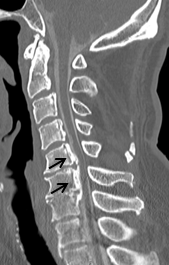

頚椎後縦靭帯骨化症(頚椎OPLL)

頚椎の椎体の後面に脊髄と接している後縦靱帯が骨化して、脊髄を圧迫する疾患です。進行すると脊髄圧迫による頚部や肩の痛み、手足のしびれ、手指の巧緻運動(細かい作業)障害、歩行障害などを生じます。

脊髄の圧迫の程度を評価するにはMRI検査が有効です。症状が軽い場合は、装具療法、薬物療法などの保存療法を行います。手指の巧緻運動障害や歩行障害が出てきた場合には、手術が必要となる可能性が高いです。

手術は前方から骨化を取り除き、骨を移植して固定する前方除圧固定術と、後方から椎弓を形成して脊髄の圧迫を解除する椎弓形成術があります。また、症状がないか軽くても転倒などの怪我で脊髄麻痺を生じることがあるので注意が必要です。なお厚生労働省特定疾患として認められています。

頚椎OPLLを認め脊髄を圧迫している状態です。前方からの骨化浮上術により症状は改善しています。